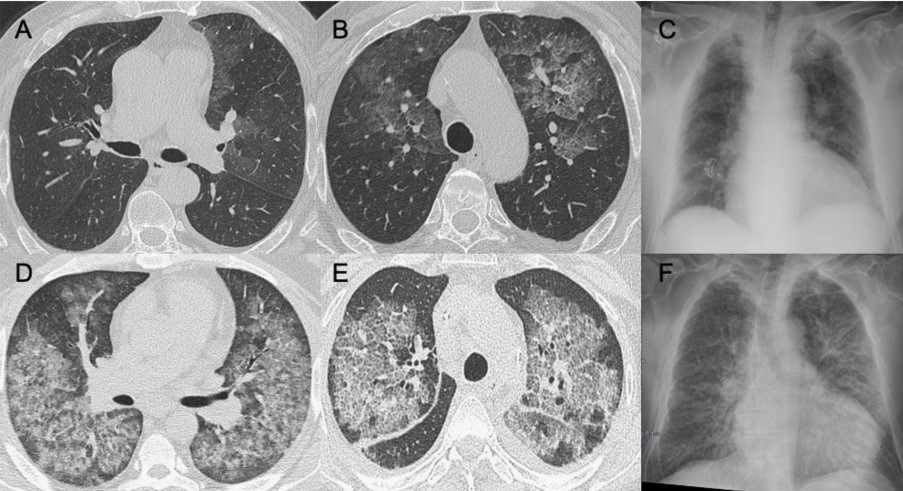

?巨細(xì)胞病毒

● CXR:彌漫性和雙側(cè)實(shí)變伴間質(zhì)受累。

● CT:間質(zhì)和肺泡浸潤,雙側(cè)和不對稱性GGO區(qū)域,與實(shí)質(zhì)實(shí)變區(qū)域相關(guān)。

圖8 巨細(xì)胞病毒性肺炎。圖(A–C)顯示其輕度實(shí)質(zhì)受累的情況。圖(D、E)顯示患者有彌漫性GGO和鋪路石征,胸片(F)中同樣可見。